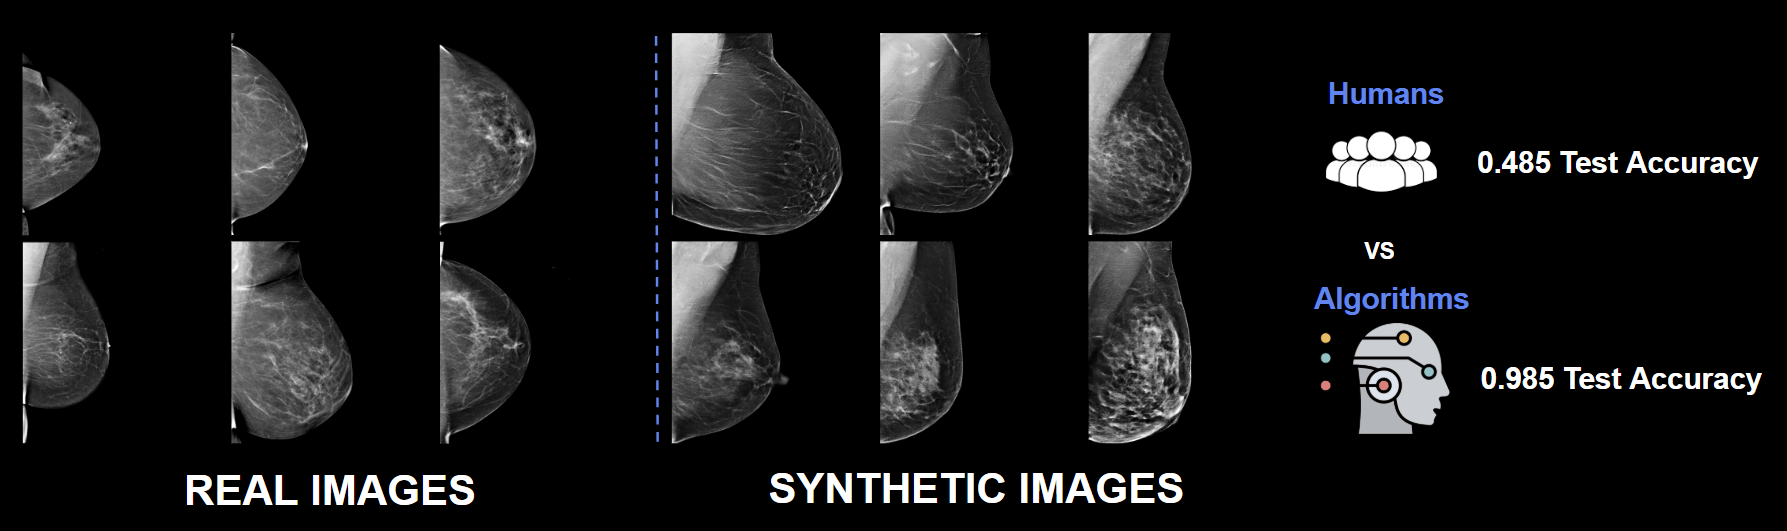

Synthetic Classifier